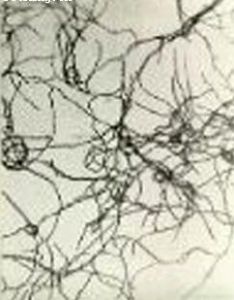

豬諾卡氏菌病是豬感染諾卡氏菌而引起的一類關節炎及關節周圍膿腫疾病,病豬經常會發生跛行等症狀。